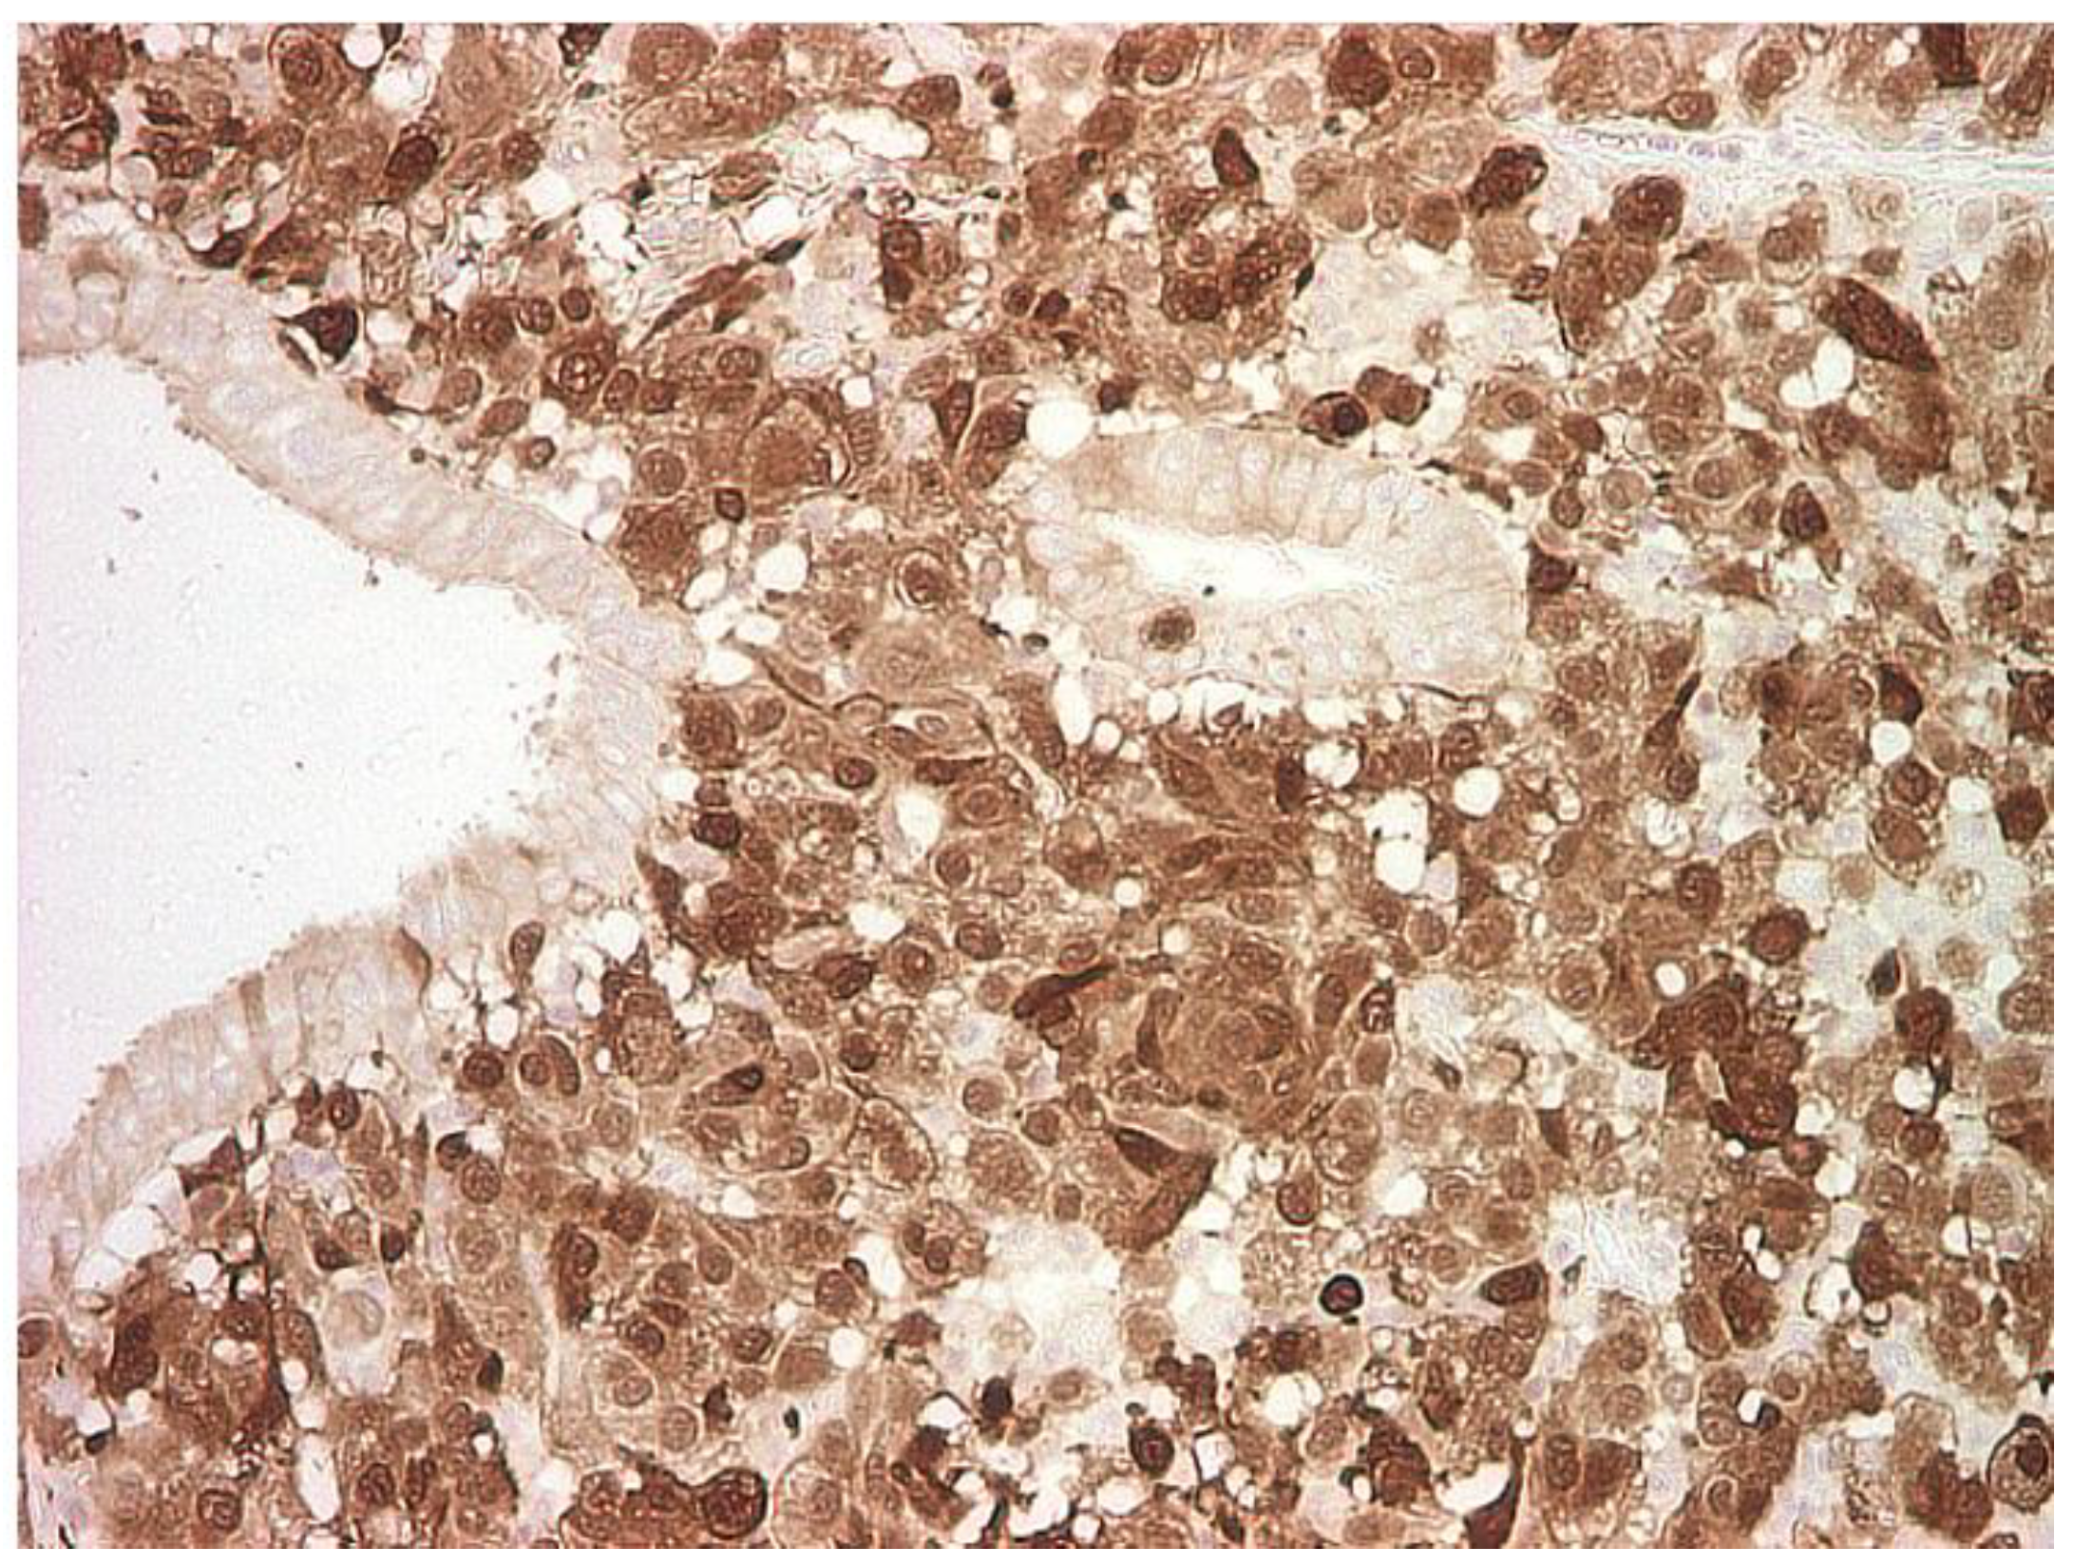

2. Case Report